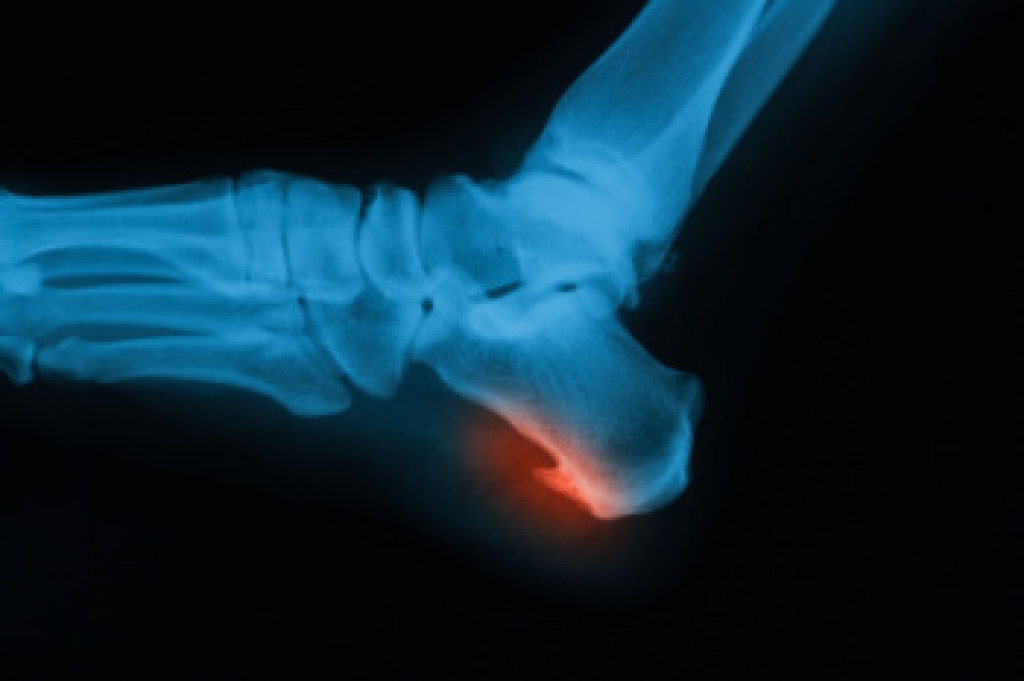

Dealing with Stress Fractures of the Foot and Ankle

Stress fractures occur in the foot and ankle when muscles in these areas weaken from too much or too little use. The feet and ankles then lose support when walking or running from the impact of the ground. Since there is no protection, the bones receive the full impact of each step. Stress on the feet can cause cracks to form in the bones, thus creating stress fractures.

Pain from the fractures occur in the area of the fractures and can be constant or intermittent. It will often cause sharp or dull pain with swelling and tenderness. Engaging in any kind of activity which involves high impact will aggravate pain.